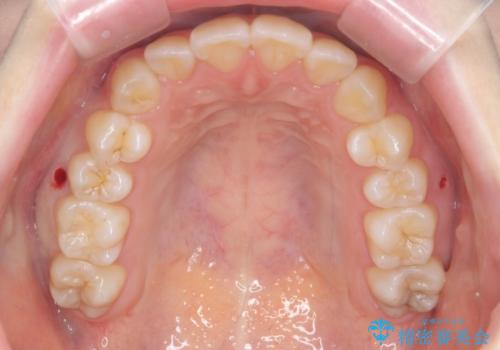

下の八重歯 歯を抜かずに インビザライン治療

- 歯並びのがたつきを主訴に来院。

抜歯してワイヤー矯正という選択肢も提案しましたが、マウスピース矯正で、歯を抜かずに並べてほしいとのことでした。

スペースを確保するために、歯をわずかに削る処置、奥歯を後ろに下げる処置(インプラント矯正)を行っています。

途中患者様のご都合で治療を中断していたため、長くかかっていますが、実質2年程度で終わる内容でした。